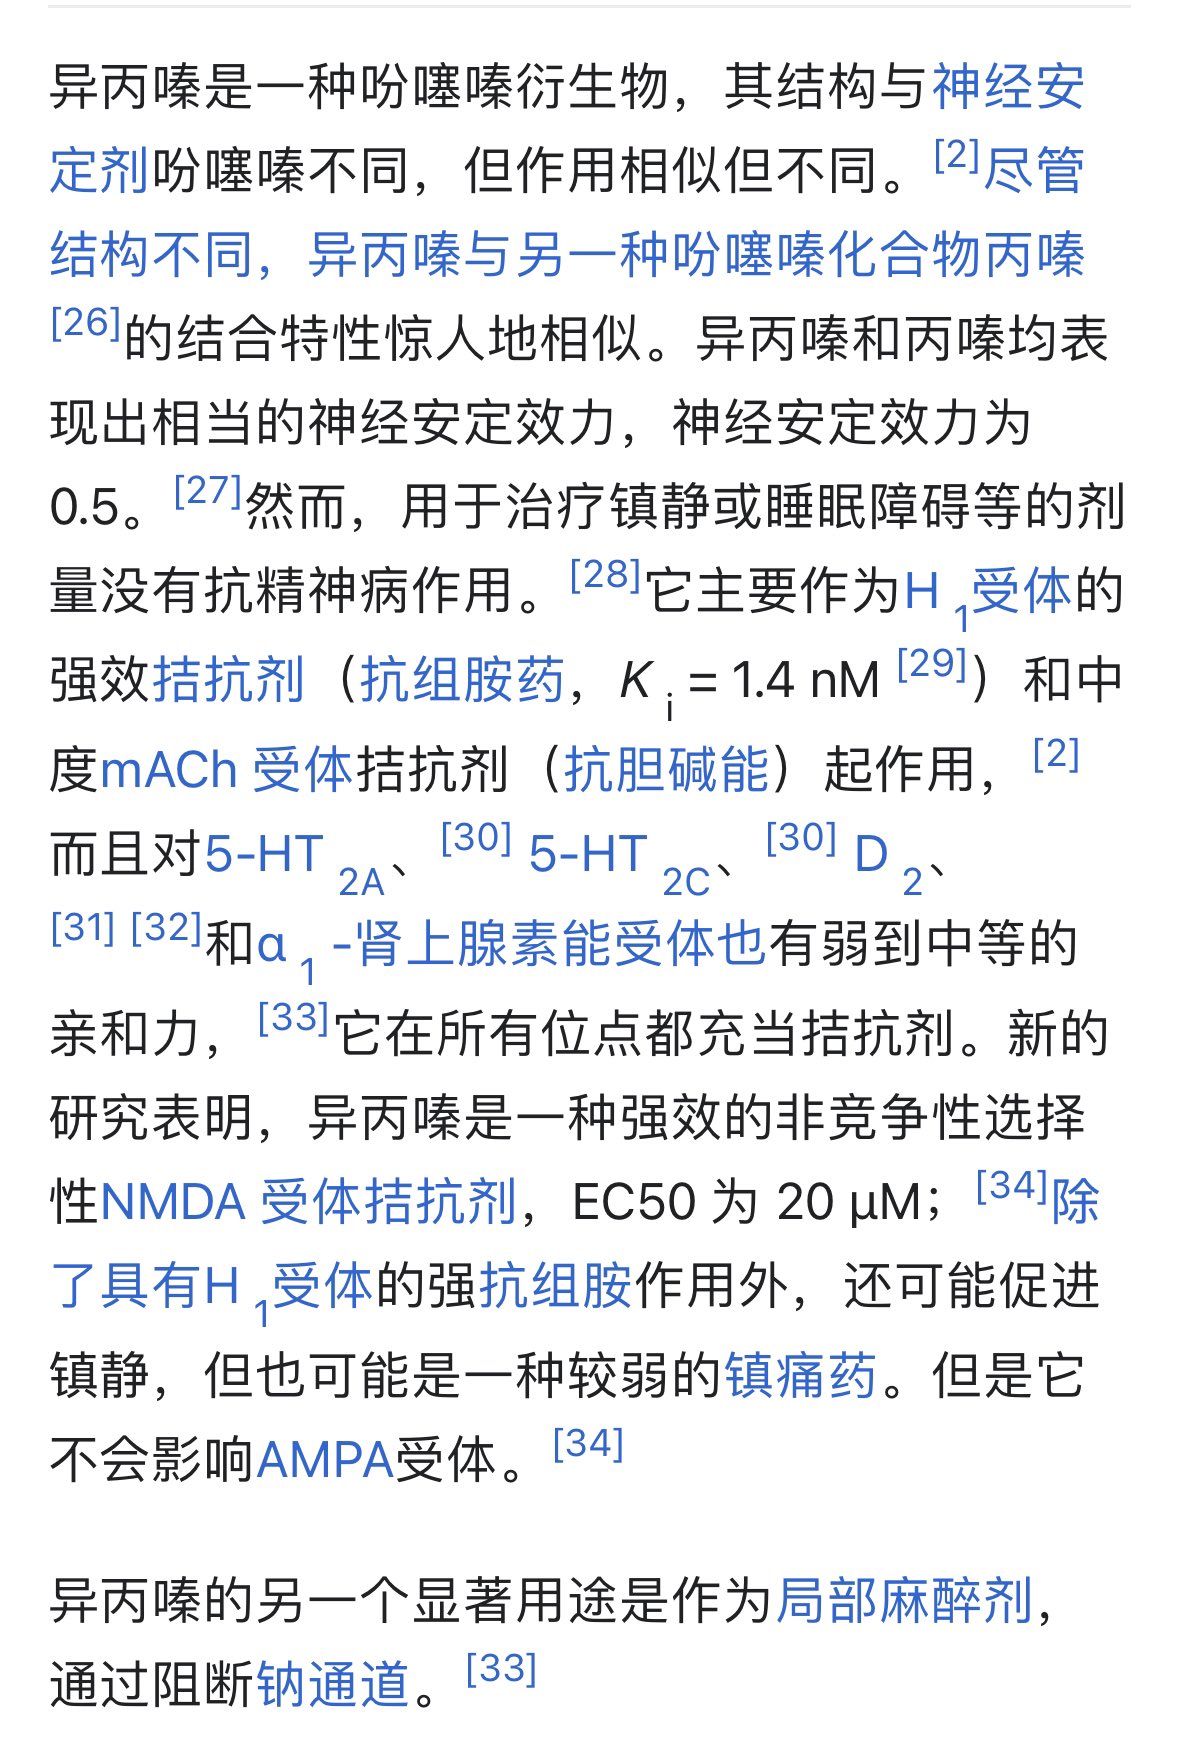

异丙嗪:在低剂量下没有抗精神病作用,和其他所有抗组胺药一样可以缓解过敏。止吐

炽烈已极 @AnIncandescence嗯...异丙嗪在其他国家被娱乐使用过,是中度抗胆碱药物,镇静,高剂量下会引起谵妄。拮抗nmda...?🤔